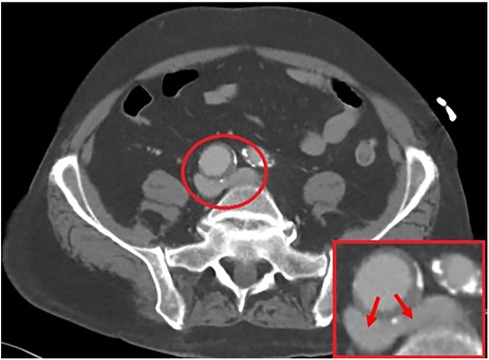

On initial evaluation, a bilateral venous duplex study was performed, which revealed thrombosis throughout the bilateral lower superficial and deep systems. A computed tomography angiography (CTA) showed compression at the bifurcation of the iliac veins due to the presence of a large 3.1 cm × 2.9 cm right CIA aneurysm, as illustrated in Figure 1. Further investigation was sought with invasive maneuvers, as discussed in management.

Figure 1. A 3.1 cm × 2.9 cm right common iliac artery aneurysm allowing for a compressive force on the bilateral iliac veins, as illustrated by the arrows.